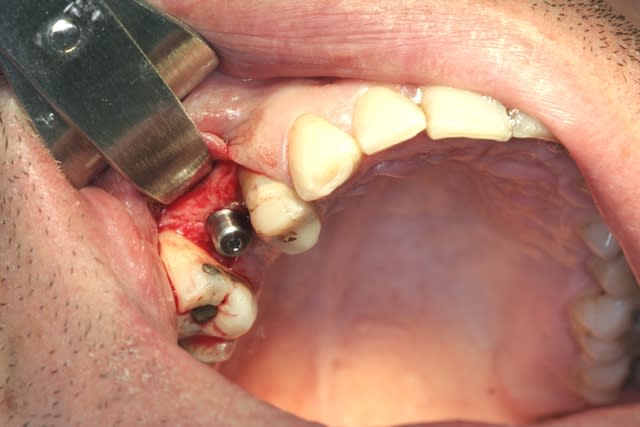

tiens...un ptit cas...

dans ce petit cas...j'ai commencé avec le kit MIS...et fini ma voie crestale avec le kit HBS...

ok, c'est un mini soulevé...mais bon , c'est un exemple...

juste une précision...premier foret 1.3mm sur 8mm...expansion pour mettre un implant de 4x10...

j'ai juste "léché" la préparation du site final avec le foret terminal du système...sur 8mm...avant d'insérer l'implant...stab primaire au top...blocage à 40 Ncm...

rien...une cloison du sinus...;-))